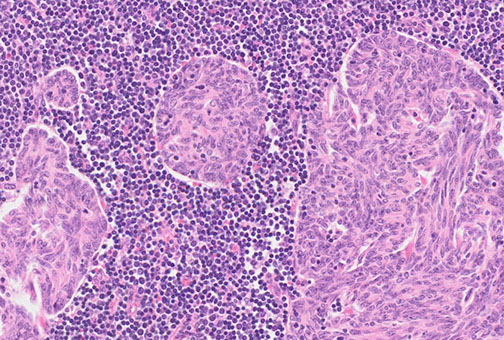

thymoma type B1

Histologically subclassified as A, AB, or B1-B3, based on "organotypical" features (i.e. histologic resemblance to normal thymic development)

- B1-B3 more epithelioid

-- B1 has more lymphs and less epithelioid cells, B3 has less lymph and more epithelioid cells

-- medullary islands essentially req'd to dx type B1

IHC: thymocytes (immature lymphs) + for CD99, CD1a and TdT; epithelial cells CK / p63+

- negative CD5 and CD117 (vs thymic carcinoma)

DDx: T-LBL, thymic hyperplasia, thymic carcinoma